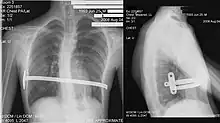

Technique de Nuss

La technique chirurgicale mini-invasive de Nuss, plus récente[16], consiste à introduire une ou deux barres à l'intérieur de la cage thoracique du patient et à les maintenir à l'aide de stabilisateurs, le tout sous contrôle thoracoscopique. Cette intervention est privilégiée pour les jeunes personnes n'ayant pas fini leur croissance (idéalement vers 15 ans, pour une ablation des barres à 18 ans, âge de fin de croissance) et possédant donc encore une structure de cage thoracique relativement souple. L'opération redresse instantanément le thorax mais empêche la pratique de sport pour un délai de 3 mois et interdit les sports de contact (rugby, karaté…) pendant toute la durée durant laquelle le patient porte la ou les barres. Cette technique nécessite une durée d'hospitalisation d'une semaine dont 4 à 5 jours sous péridurale. Plus cette opération est pratiquée tôt, moins les douleurs physiques sont grandes (croissance des cartilages). Le matériel est généralement enlevé trois années après avoir été mis en place, une fois que la structure osseuse est solidifiée (transformation des cartilages osseux en os solides, due à l'âge). Le rapport risques/bénéfices de la technique de Nuss est cependant remis en cause du fait de la gravité des complications médicales qui peuvent résulter d'un déplacement de la barre (notamment des perforations cardiaques ou des interruptions de la veine cave)[17].